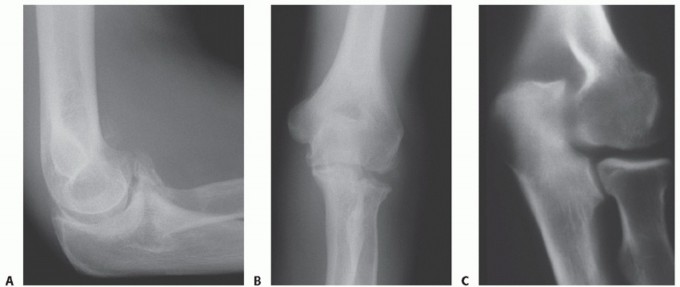

DEFINITION Primary osteoarthritis of the elbow is a relatively uncommon but disabling disorder that affects m…

DEFINITION Posttraumatic conditions of the elbow represent a variety of disorders involving the elbow as a re…

DEFINITION Extrinsic elbow contracture refers to elbow stiffness secondary to fibrosis, thickening, and, occa…